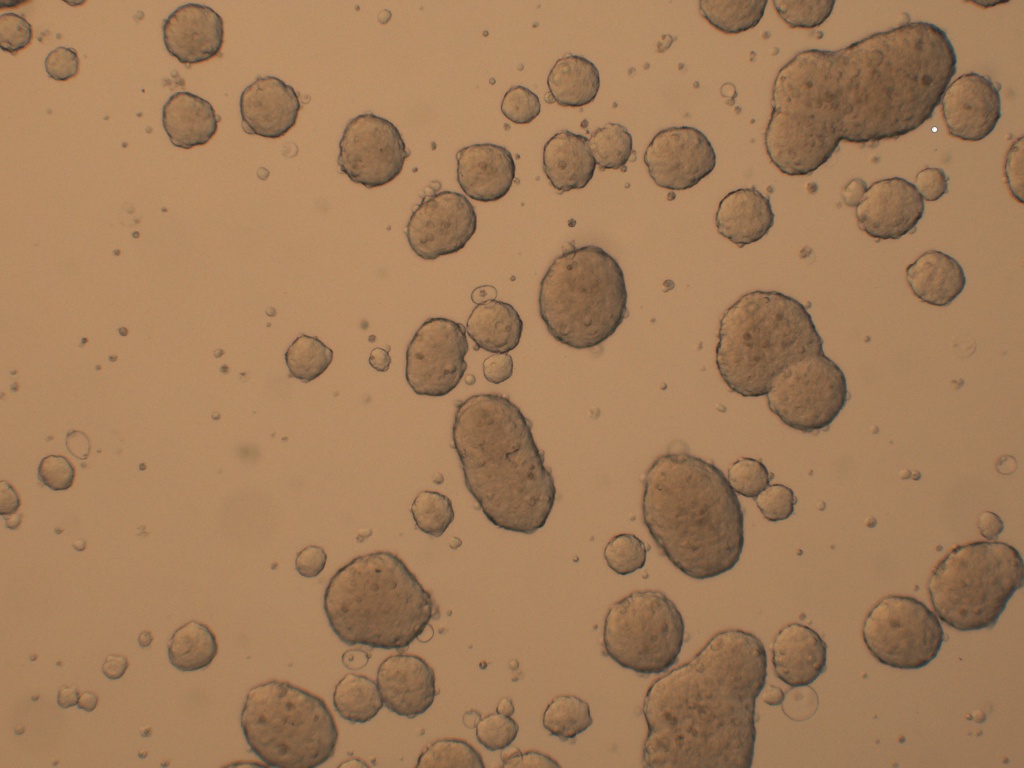

Cancer Stem cells Spheres Medium(肿瘤干细胞成球培养基)是一款用于将癌症干细胞(CSC)培养成3D球的培养基���。癌症干细胞(CSC)被定义为肿瘤内的一小部分细胞���,具有自我更新的能力����,并且经常在化学疗法治疗后驱动肿瘤的进展和复发����。因此����,针对CSC的特定疗法的开发有望改善癌症患者的生存和生活质量���,特别是对于患有转移性疾病的患者�����。

肿瘤干细胞成球培养基是一种新的化学成分确定和无血清的癌症干细胞培养基�����,可支持CSC形成3D球状细胞的聚集和扩增�����。

7、 4-10 天左右在超低吸附板孔中央区域会形成肿瘤球体;